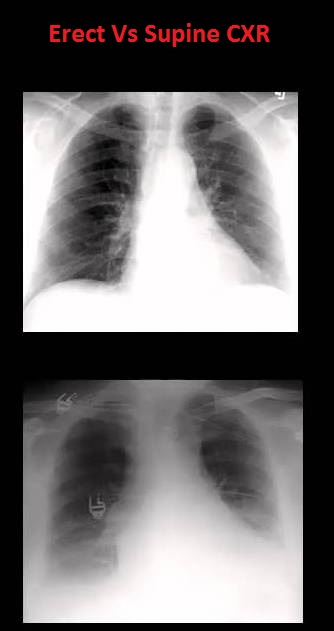

2. Erect vs Supine position

| Erect (A) vs Supine (B) chest xray |

There is fundal view in erect position because all the air in stomach comes in fundus when the patient is standing.